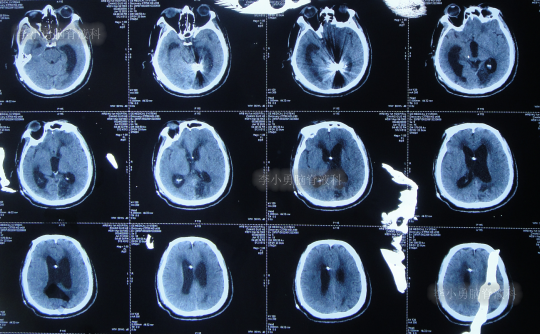

2022年6月13日(脑室腹腔分流术后5天),术后患者仍走路不稳,有时胡言乱语,言语不清,小便失禁,查头颅CT(图-8)示脑室仍有扩张。

图-8:2022年6月13日头颅CT

2022年6月17日(分流术后9天即第2次该院治疗53天),查头颅CT虽仍有脑积水(图-9),但仍让患者出院,出院时:仍走路不稳,有时胡言乱语,言语不清,小便失禁;转至当地的某医院进行治疗。

图-9:2022年6月17日头颅CT

在当地的某医院进行康复治疗1个月的时间,患者症状无改善,期间3次查头颅CT(图-10、图-11、图-12)均示仍脑积水。

图-10:2022年6月20日头颅CT

图-11:2022年7月1日头颅CT

图-12:2022年7月12日头颅CT